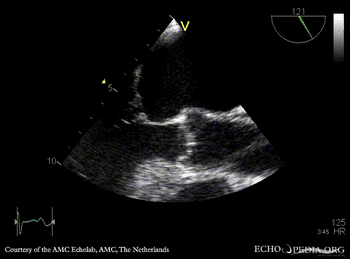

PLAX: Color Doppler, severe mitral regurgitation, excentric jet A4CH: thickend PMVL, prolaps of PMVL